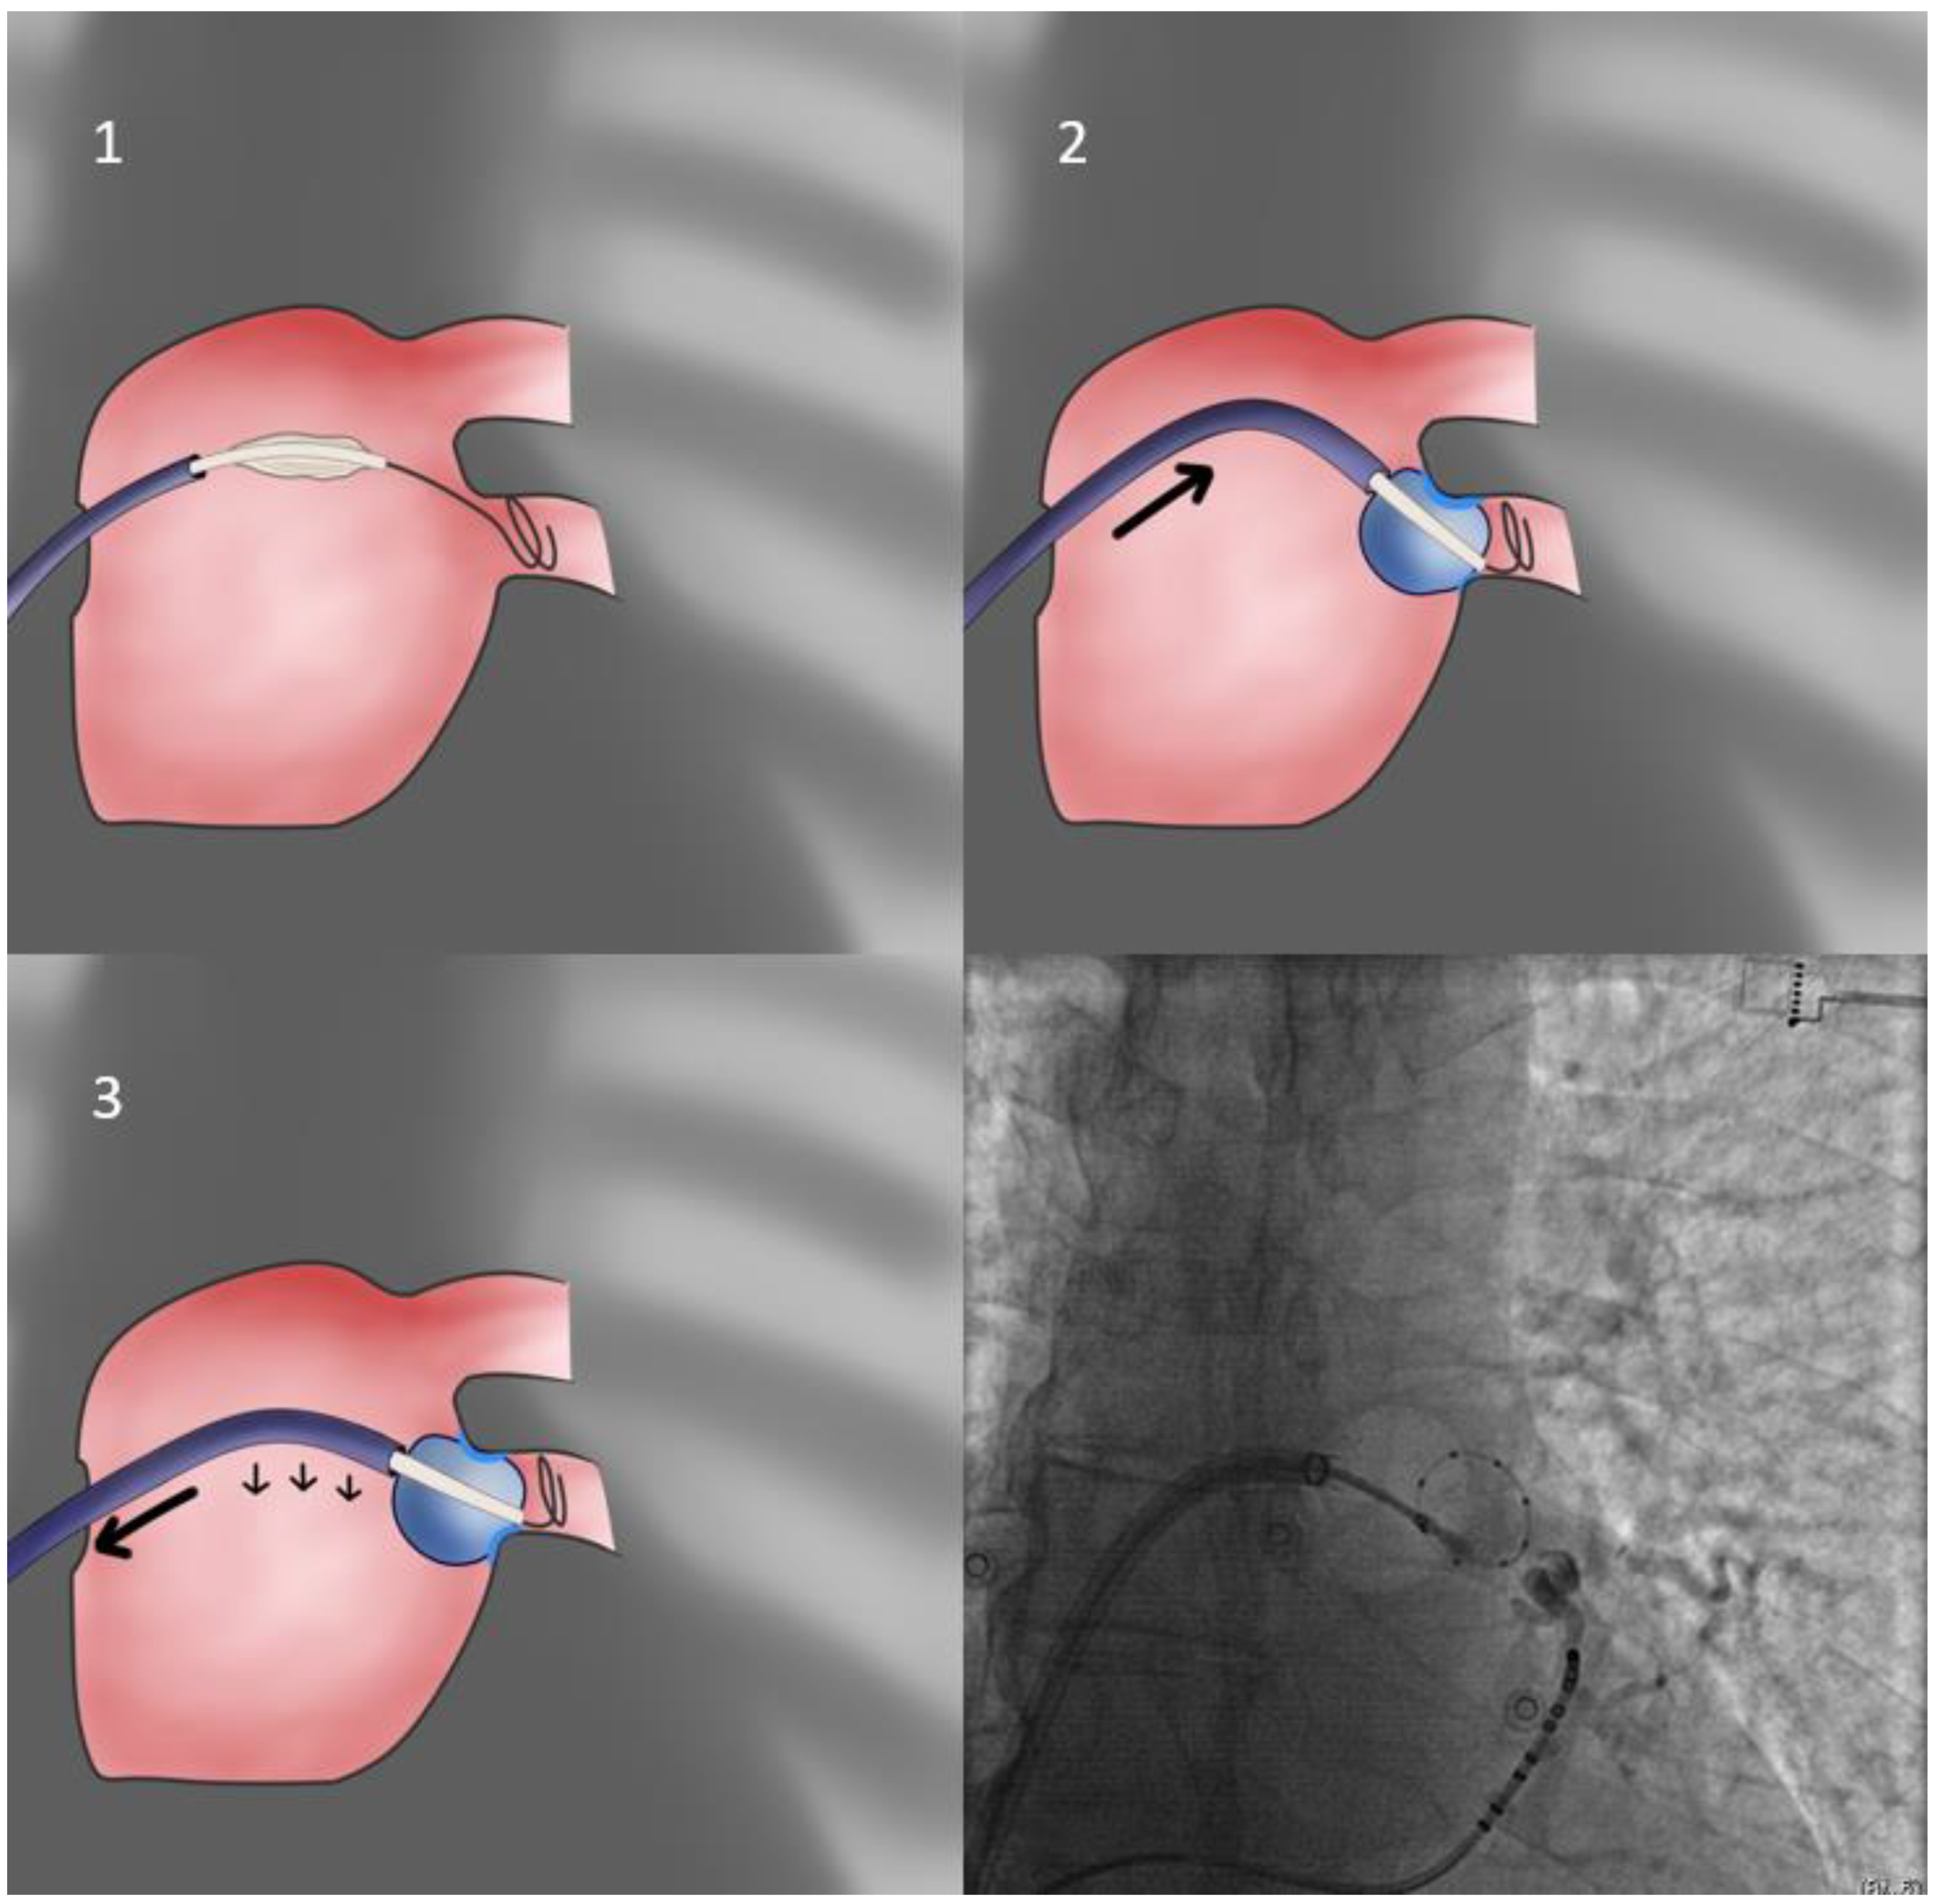

- In cases of cranial superior veins and horizontal inferior veins, we apply the CB-only approach (Figure 3) without the sheath (second approach). The sheath is relaxed and placed near but not in contact with the CB since even minimal flexion to the sheath will preclude proper sealing of the antrum. Selection of the more horizontal branch of the PV facilitates the CB-only approach, even if repositioning of the Achieve catheter is required. Additionally, cranial flexion of the CB shaft assists cranial superior PV sealing.